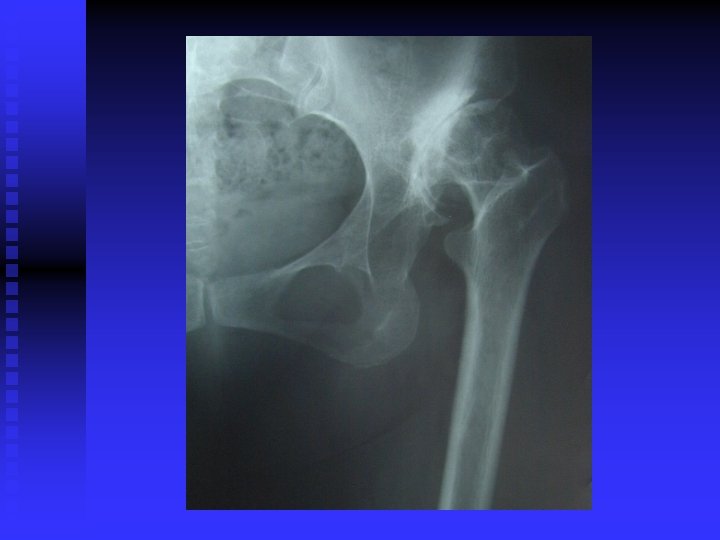

OA RÖNTGEN BULGULARI n Eklem aralığında daralma (kıkırdak incelmiş) n Eklem aralığının kalmaması (kıkırdak bitmiş) n Yük binen yerlerde kistler n Yük binmeyen yerlerde osteofitler